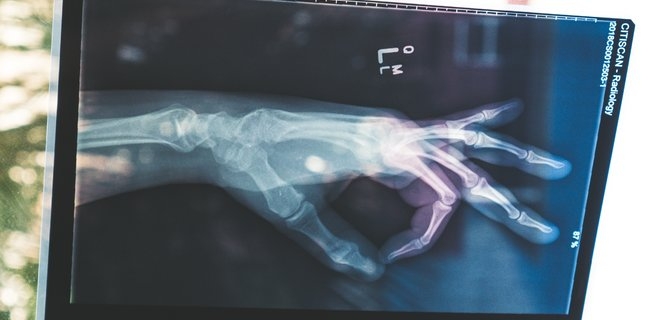

Ученые из Университета Нового Южного Уэльса (UNSW) представили решение, позволяющее печатать кость с использованием живых клеток и без использования агрессивных химикатов непосредственно внутри тела пациента.

Новая технология работает следующим образом: специально разработанный материал помещают в желатиновую ванну (для имитации человеческого тела) и вызывая химическую реакцию превращают пасту в пористую структуру, похожую на настоящую кость, которую она заменяет.

“Это действительно первый пример интеграции керамических материалов, которые имитируют многие аспекты естественной кости с живыми клетками”, – говорит исследователь проекта Крис Килиан. “Это действительно открывает возможность напечатать кость пациента непосредственно внутри полости”.

Стоит отметить, что ученые в своей работе использовали стандартный 3D-принтер Hyrel 3D Engine HR со специально разработанной насадкой.